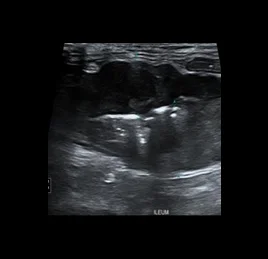

초음파 검사는 고주파 음파를 이용해 장기와 조직의 실시간 움직임을 영상으로 확인하는 비침습적 진단법입니다.

장기의 구조뿐 아니라 혈류, 운동성, 기능 변화까지 평가할 수 있어, 다양한 질환의 조기 발견과 모니터링에 효과적입니다.

📍초음파 진단 케이스

• 소장 종양